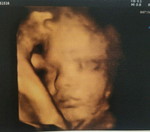

แม่ท้องได้31สัปดาห์ ทานดีคอลเจนได้ไหมคะ